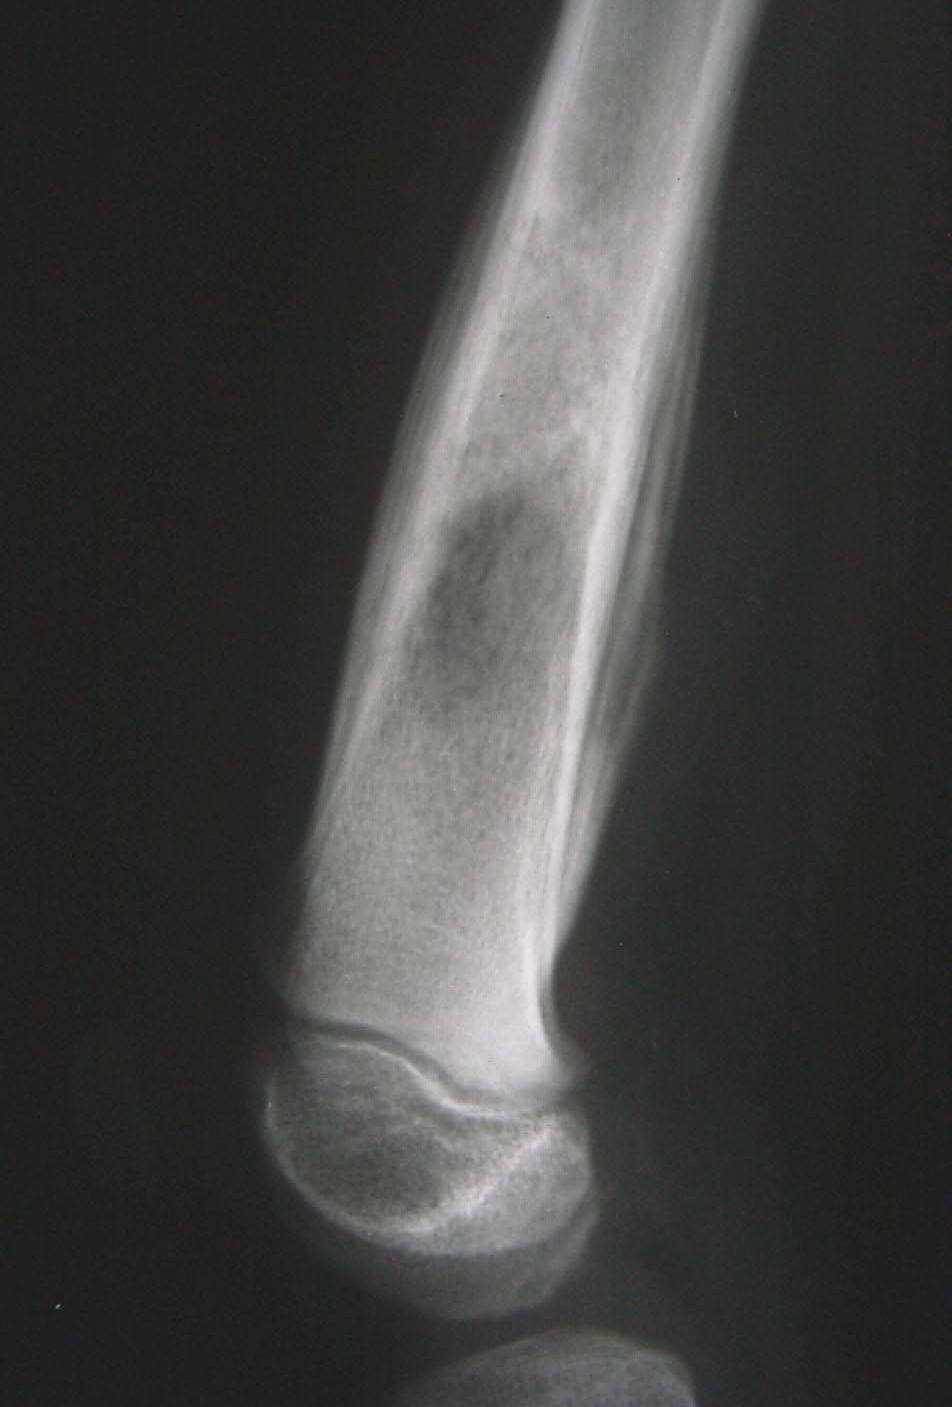

瘤软骨钙化

瘤软骨常表现为环状钙化, 是诊断软骨类肿瘤较为可靠的影像学征象。环状钙化形成于环状软骨、以及软骨小叶边缘的软骨基质。钙质沉着可呈小点状、小条状、半环状或弧形;亦可浓密相连、重叠呈菜花状。钙化环的形态和密度可反映瘤组织分化程度, 通过观察钙化环的形态和密度,有助于良恶肿瘤的鉴别。良性瘤软骨之瘤细胞分化好、生长缓慢、血供充分, 钙化环完整,密度高, 边缘清楚。良性软骨类肿瘤如骨软骨瘤(图 35)、软骨母细胞瘤(图 36)、内生软骨瘤(图 37)等均可于瘤组织内发生环形钙化。恶性瘤软骨则呈密度淡薄, 边缘模糊的不规则钙化,恶性骨肿瘤的环形钙化,最多见于软骨肉瘤(图 38),其次是骨肉瘤。CT 是发现肿瘤内软骨钙化最为敏感的检查方法。

图 37.瘤软骨钙化:内生软骨瘤

图片